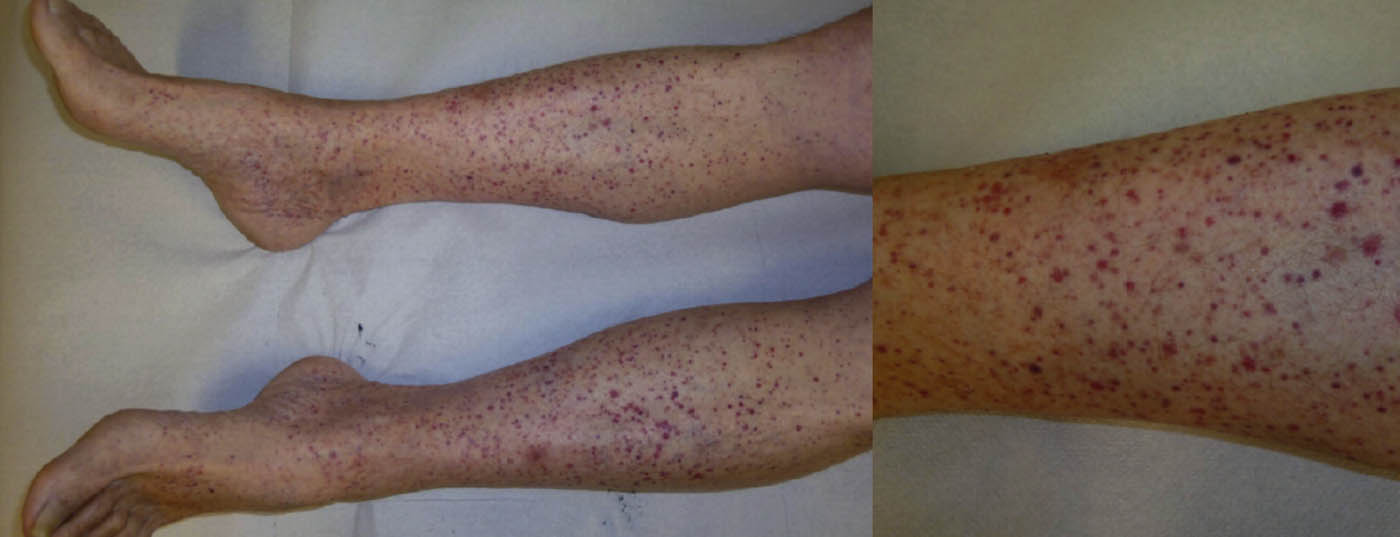

Die Vaskulitiden sind eine sehr heterogene Gruppe von Erkrankungen, welche in allen Altersgruppen auftreten können. Im Prinzip handelt es sich um Entzündungsvorgänge in den Gefässwänden mit nachfolgender Gewebeschädigung. Die klinische Bandbreite ist gross und reicht von der wenig symptomatischen, selbstlimitierenden und auf die Haut beschränkten Vaskulitis bis hin zur lebensbedrohlichen Systemvaskulitis.